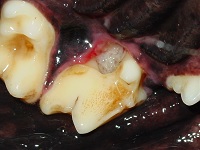

A 6 year-old Cross breed dog is presented with halitosis.  On examining the oral cavity you see the following:

The accompanying photo shows a different case that developed osteomyelitis around the 208 after a transpalatal foreign body was removed.